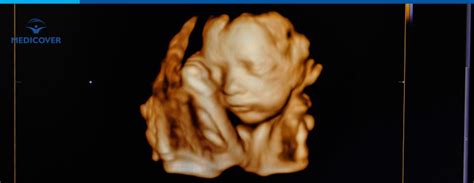

Investigația se numește „Dublu Test” pentru că presupune efectuarea a două etape în aceeași zi - ecografie morfologică fetală și analiză de sânge (markeri biochimici fetali) - la mai puțin de 24 de ore distanță una față de cealaltă.